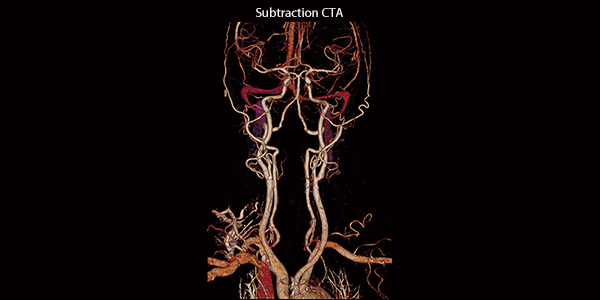

Передовые клинические решения Canon Medical гарантируют превосходную визуализацию сосудистой сети в исследованиях CTA, в то время как Iodine Mapping обеспечивает дополнительный уровень детализации в рамках

Вычитание СТА

Превосходная визуализация в CTA с истинным вычитанием кости и кальция

- SURE Subtraction автоматическое вычитание кости